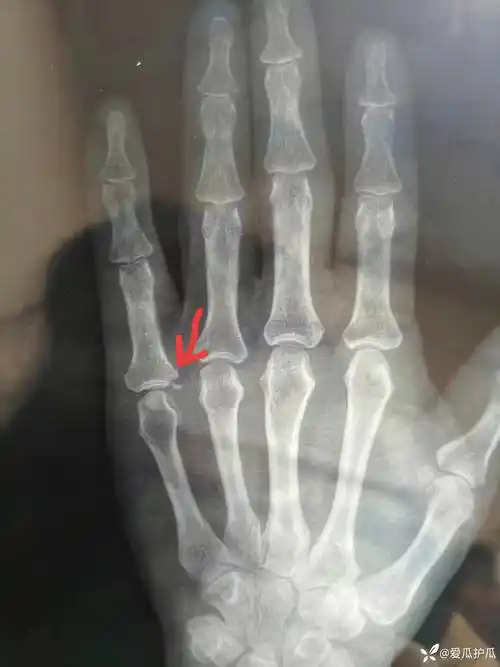

工伤指骨骨折想马上知道能评几级!

拇指近节指骨骨折